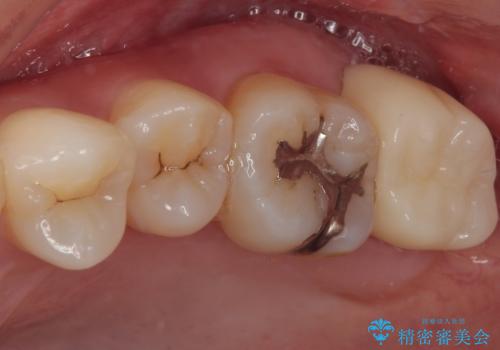

- 元々むし歯があったものの、処置が困難とのことでしたが、矯正治療を終えたので処置をしたいとのことで来院された患者様です。

左右ともに最後臼歯が頬側に顕著に突出しており、むし歯になってしまったことが想像されました。

矯正治療により処置が可能な位置に歯が移動したため、オールセラミッククラウンにて補綴治療を行うこととしました。

歯列が移動したとはいえ、左右ともに後方傾斜しており、むし歯の除去、形成(形を整える)、型取りの全てが非常に困難な処置となりました。